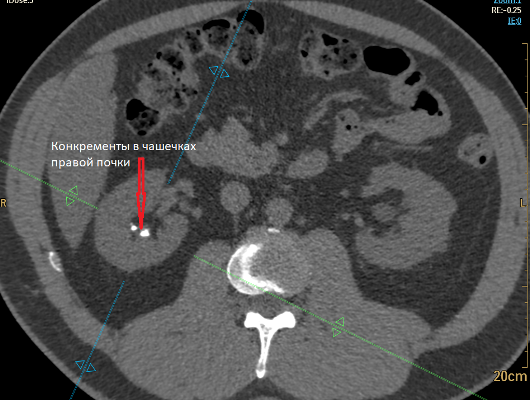

Функция почек своевременная. ЧЛС почек правильно сформирована, не расширена. Мочеточники обеих почек на уровнях сканирования не расширены. В ЧЛС правой почки видны конкременты – в нижней и средней группах чашечек (два), размерами до 3-6 мм (показатели плотности до 800 HU). На уровне средней трети левого мочеточника, в его просвете, определяется конкремент 5х3 мм, после контрастирования в выделительной фазе отмечается омывание конкремента, дистальные отделы мочеточника прослеживаются.

РКТ-картина конкрементов в нижней и средней группе чашечек правой почки; конкремента в просвете левого мочеточника. КТ-признаки жирового гепатоза.